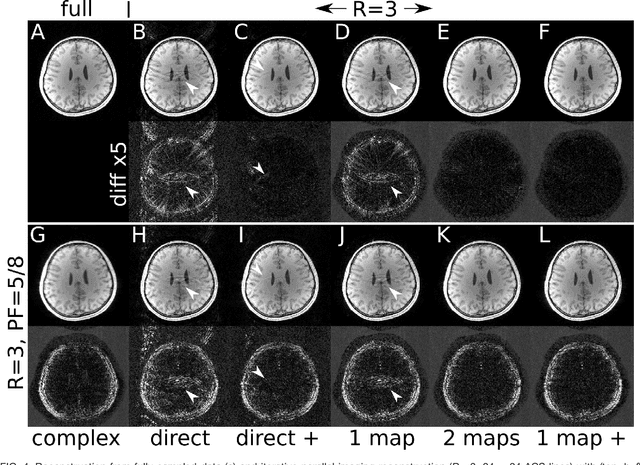

Abstract:Purpose: In this work, we present a workflow to construct generic and robust generative image priors from magnitude-only images. The priors can then be used for regularization in reconstruction to improve image quality. Methods: The workflow begins with the preparation of training datasets from magnitude-only MR images. This dataset is then augmented with phase information and used to train generative priors of complex images. Finally, trained priors are evaluated using both linear and nonlinear reconstruction for compressed sensing parallel imaging with various undersampling schemes. Results: The results of our experiments demonstrate that priors trained on complex images outperform priors trained only on magnitude images. Additionally, a prior trained on a larger dataset exhibits higher robustness. Finally, we show that the generative priors are superior to L1 -wavelet regularization for compressed sensing parallel imaging with high undersampling. Conclusion: These findings stress the importance of incorporating phase information and leveraging large datasets to raise the performance and reliability of the generative priors for MRI reconstruction. Phase augmentation makes it possible to use existing image databases for training.